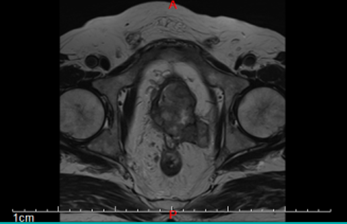

| 影像学检查:(点击查看大图) | 平扫:前列腺区见多发结节融合成团状异常信号,形态不规则、局部呈菜花状改变,边界欠清,范围约61mm×34mm×64mm,病变在T1WI上呈等信号,在T2WI上信号不均匀,呈等信号内见不规则团片状稍高信号,周围脂肪间隙模糊,病变与双侧精囊腺、膀胱后壁、直肠后壁、左侧闭孔内肌分界不清,直肠下段前部脂肪间隙消失,左侧精囊角消失;膀胱充盈欠佳,膀胱壁不规则稍增厚,最厚径约7mm。盆腔、双侧腹股沟、髂血管旁区见多发肿大淋巴结,较大大小约22mm×14mm。 增强:前列腺区见病变呈不均匀轻度环形强化,病变侵犯邻近直肠,相应肠管管壁增厚呈类似强化;盆腔、双侧腹股区、髂血管旁区肿大淋巴结呈轻度不均匀强化。增厚膀胱壁呈明显强化;余未见异常强化表现。 与2023-09-23 前列腺MRI对比:前列腺癌术后改变,前列腺区见多发结节融合成团状异常信号,新见左侧闭孔内肌、直肠后壁受累,左侧精囊角消失,髂血管旁区见多发肿大淋巴结,盆腔、双侧腹股沟淋巴结较前稍增多,其余所见大致相仿。 影像诊断意见: 前列腺癌(UICC分期:T4N1Mx IV期),双侧精囊腺、膀胱后壁、直肠后壁、左侧闭孔内肌受累,盆腔、双侧腹股沟、髂血管旁区见多发肿大淋巴结,复查病变较前进展。 |